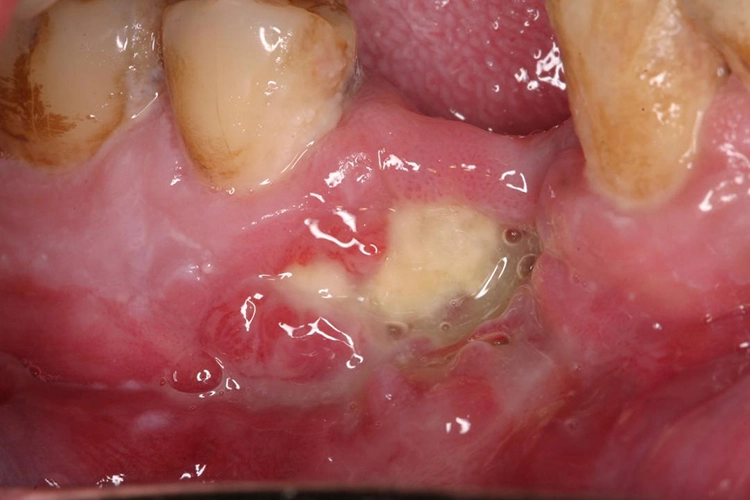

Bei einfachen zahnärztlich-chirurgischen Eingriffen ist die Regenerationsfähigkeit des Knochens deutlich gesenkt. Die Bezeichnung der medikamentenassoziierten Osteonekrose des Kiefers (MRONJ = „medication-related osteonecrosis of the jaw“) wird definiert durch folgende Punkte:

- mehr als 8 Wochen exponierter nekrotischer oder sondierbarer Kieferknochen

- laufende oder frühere Einnahme von antiresorptiven oder antiangiogenetischen Medikamenten

- keine Kopf-Hals-Radiatio in der Anamnese

| 1 | – exponierter oder sondierbarer, nekrotischer Knochen – asymptomatischer Befund – keine Anzeichen von Infektionen |

| 2 | – exponierter oder sondierbarer, nekrotischer Knochen, – symptomatischer Befund (Schmerzen, Entzündungszeichen) – Anzeichen von Infektionen |

| 3 | Zusätzlich zu Stadium 2 noch mindestens eines der folgenden Symptome: – exponierter nekrotischer Knochen, der sich auf benachbarte Regionen (Kieferhöhle, Jochbein, Unterkieferbasis) ausbreitet – pathologische Frakturen – extraorale Fisteln – Mund-Antrum-Verbindung (MAV) |

Die Stadien 0 und 1 können konservativ mit Spülungen und ggf. Antibiotikatherapie behandelt werden. Allerdings gilt es zu bedenken, dass nekrotischer Knochen nicht wieder vital wird und somit eine dauerhafte Infektionsquelle darstellt. In neueren Studien konnte deshalb auch gezeigt werden, dass nach chirurgischer Intervention, auch in den Stadien 0 und 1, eine deutlich höhere Heilungsrate verzeichnet werden konnte als bei rein konservativer Therapie [3,13,21].

Bei chirurgischer Intervention soll eine atraumatische OP-Technik angewendet werden. Dazu gehören das Glätten scharfer Knochenkanten im Sinne einer modellierenden Osteotomie und eine plastische Deckung der Wunden durch einen spannungsfreien Wundverschluss.